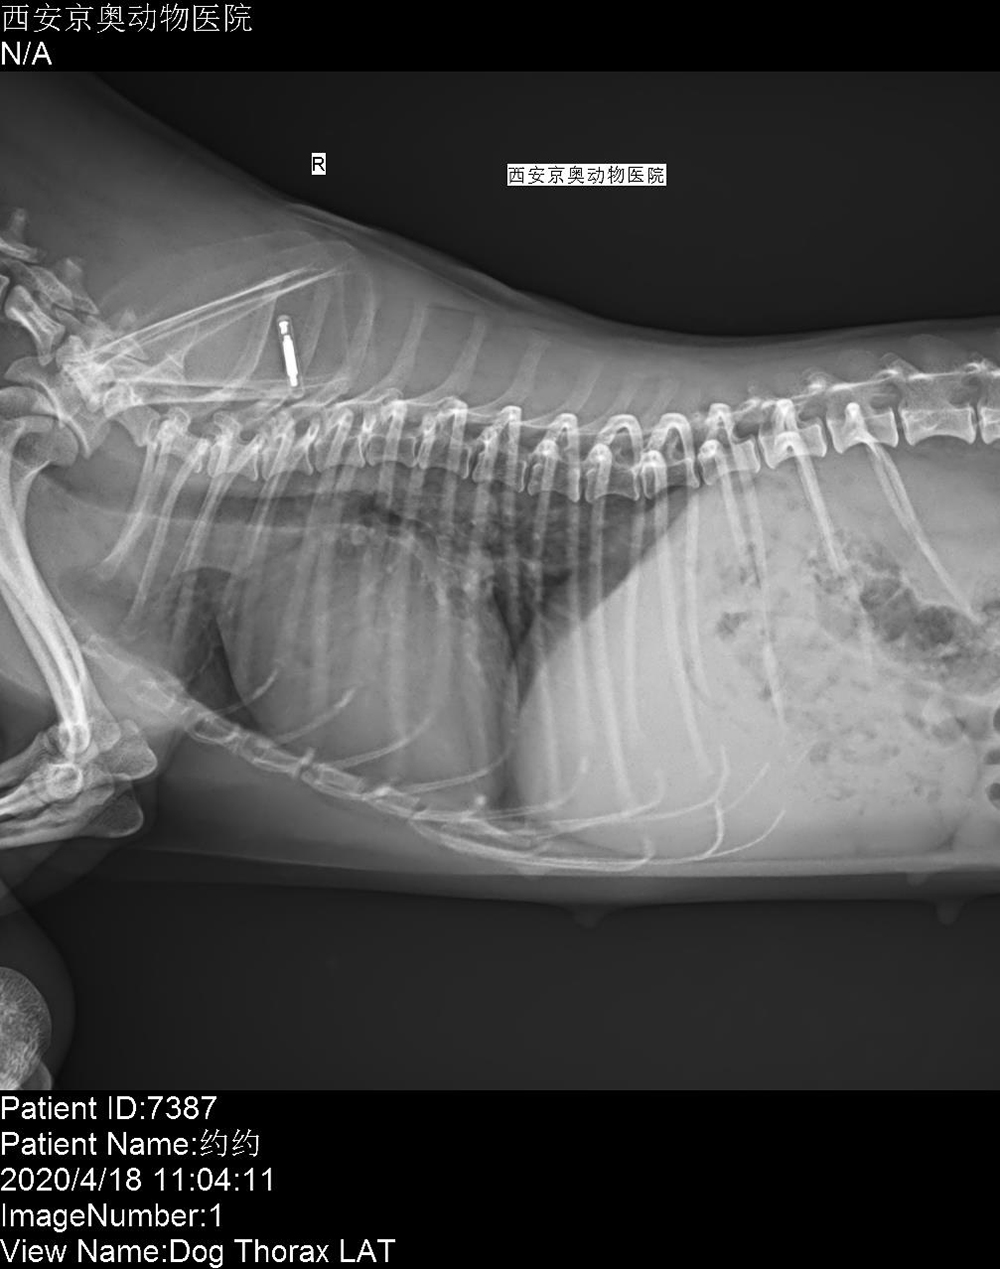

陝西(xī)西(xī)安京奧動物(wù)醫(yī)院 2020/4/14 上(shàng)一(yī)篇: 山(shān)東(dōng)青島欣康寵物(wù)醫(yī)院 下(xià)一(yī)篇: 湖(hú)北(běi)武漢博菲克動物(wù)醫(yī)院